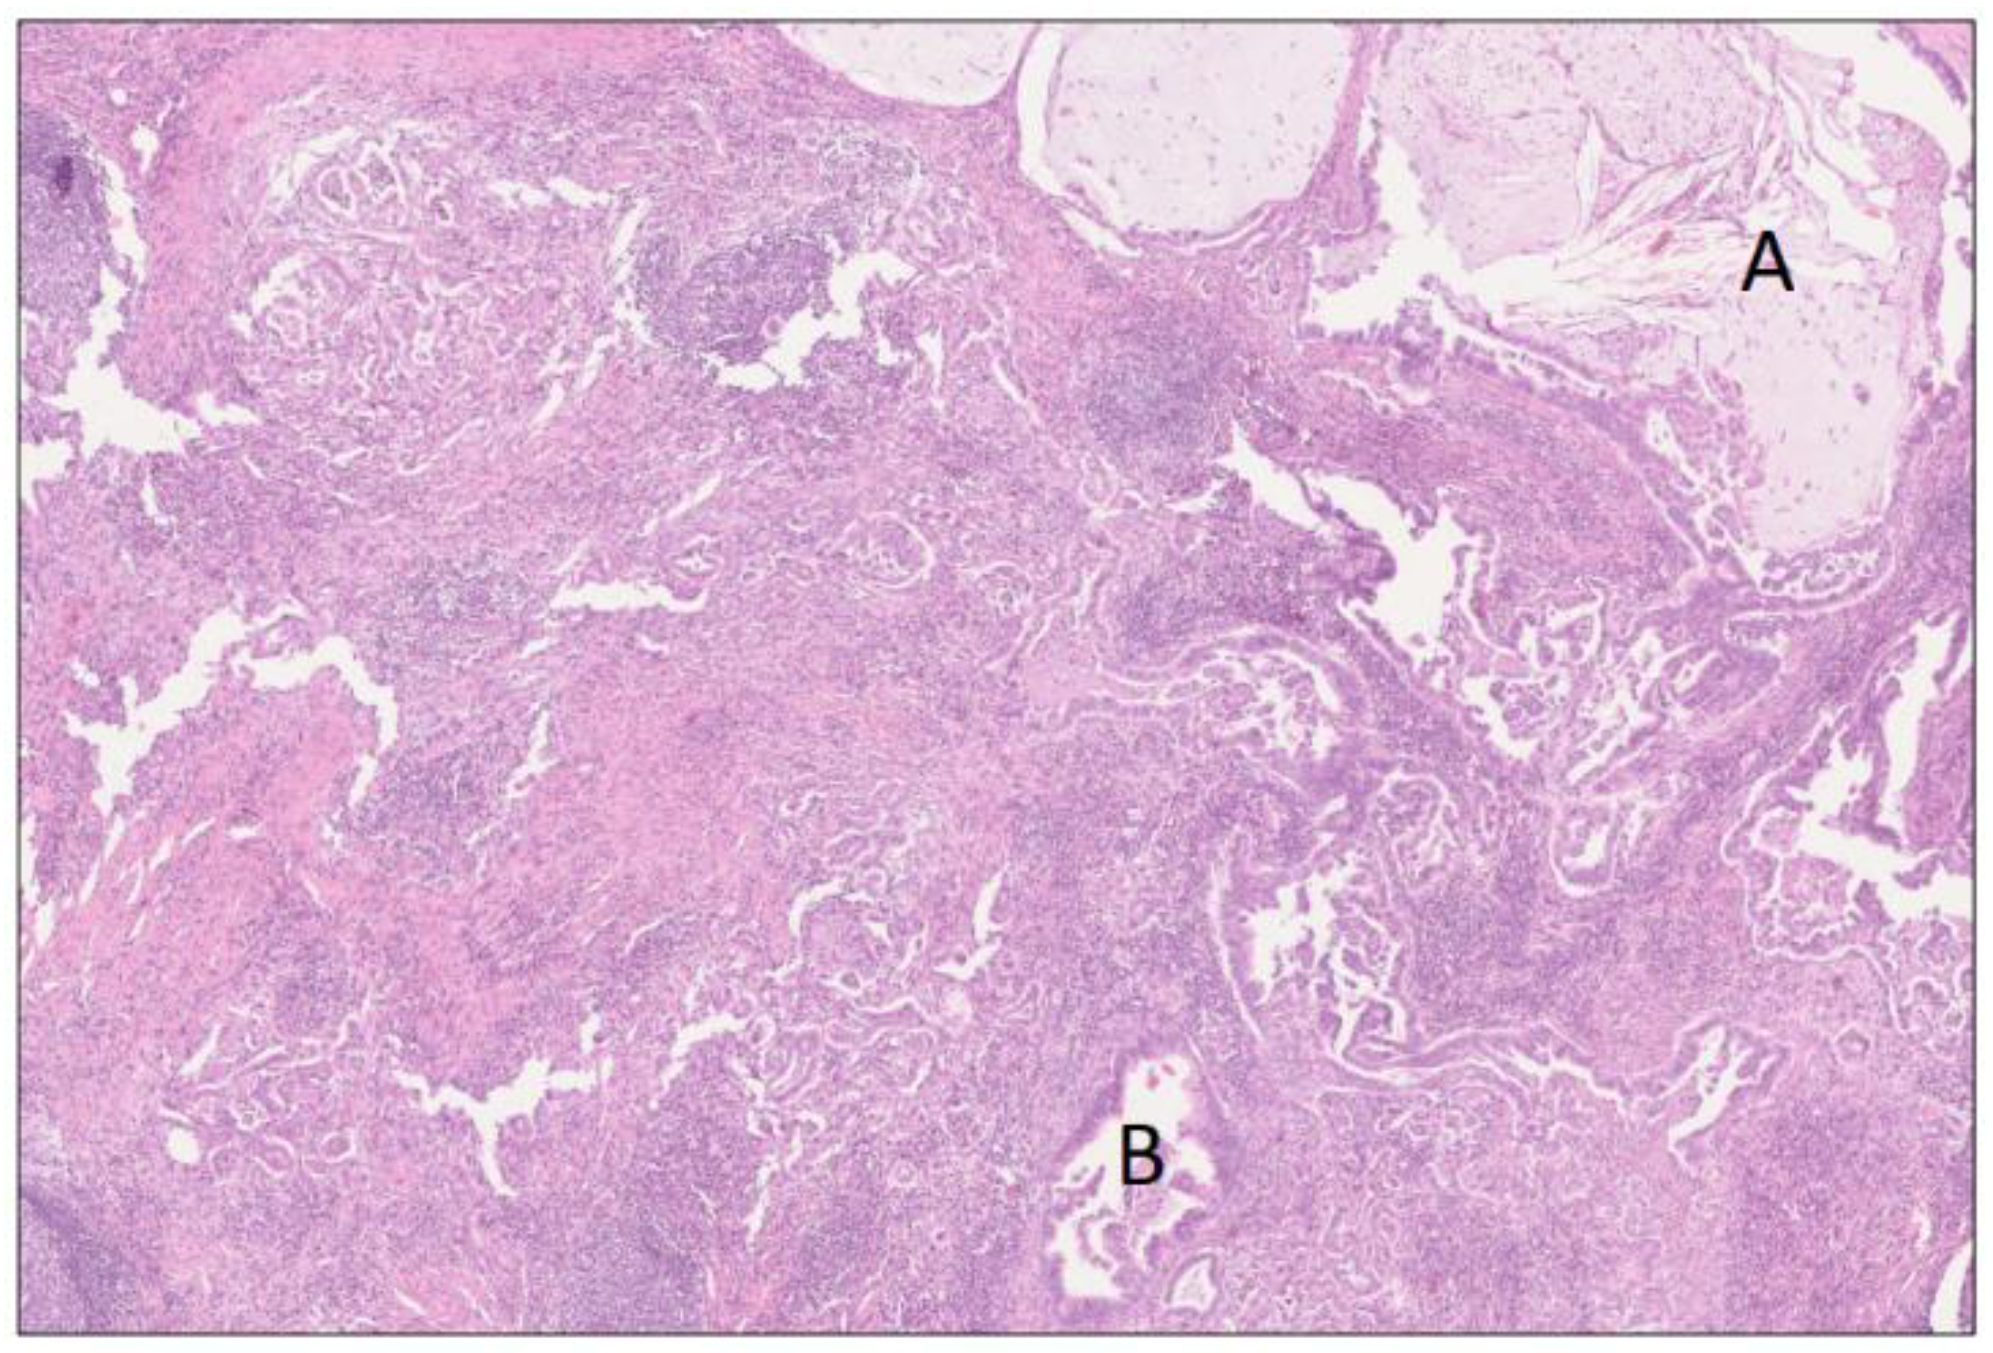

A 68-year-old female presented at a primary care outpatient clinic in January 2020 due to abdominal pain, weight loss (11 kg in total in one year), and frequent (7–9 per day) watery stools (sometimes fatty/oily stools). The patient had a 45-year history of smoking (approximately 15 pack-years of smoking) and very rarely drank alcohol. She had a 20-year history of kidney stones, and her abdominal pain disappeared after treatment with non-steroid anti-inflammatory drugs (NSAIDs) and tramadol. The patient was clinically diagnosed as suffering pain related to kidney stones, which was confirmed with computed tomography (CT) of the kidneys showing five stones < 5 mm in the right kidney and three stones < 5 mm in the left kidney. Routine laboratory results showed slightly elevated liver function tests (aspartate aminotransferase 0.7 μkat/L, alanine transaminase 1.05 μkat/L, and alkaline phosphatase 2.2 μkat/L), and CT of the abdomen and pelvis was performed (Figure 1a,d). In summary, there were inflammatory changes in the head of the pancreas, hepatoduodenal ligament, and peripancreatic fat, wall thickening of the second part of the duodenum, presence of cystic lesions in the pancreatic groove, and head and regional lymphadenopathy. Additionally, there was dilatation of the common bile duct (1.6 cm) and mild dilatation of the main pancreatic duct in the body and tail of the pancreas (5 mm) (Figure 1a,d). Gastroscopy in January 2020 showed mild bleeding of the edematous and vulnerable mucosa in duodenal pars descendens. The endoscopist described in the report that in this part of the duodenum the passage was somehow difficult and the expansion of the duodenal lumen after CO2 insufflation was not fully successful. There were no signs of ulcerations or tumor. Biopsy was performed, and the histopathology showed normal mucosa and Brunner glands. The patient was referred to a surgeon (February 2020), who started treatment with esomeprazole (due to the endoscopic findings) and pancreatic enzyme replacement therapy (PERT) (due to the history of weight loss and steatorrhea). The case was presented and discussed at the multidisciplinary team (MDT) pancreas conference at our hospital, and the team recommended CT of the pancreas and endoscopic ultrasound (EUS). CT of the pancreas (February 2020) confirmed the findings of inflammatory changes in the head of the pancreas, hepatoduodenal ligament, and peripancreatic fat, wall thickening of the second part of the duodenum (more prominent changes in the medial aspect of duodenum compared to the examination in January 2020), regional lymphadenopathy and dilatation of the common bile, and mild dilatation of the main pancreatic duct in the body and tail of the pancreas (Figure 1b,e). One of the cystic lesions in the head of the pancreas increased from 2 to 2.5 cm, whereas another cystic lesion in the pancreatic groove decreased from 2 to 1 cm.

In December 2020, the patient came for a clinical check-up at the pancreatic outpatient clinic. Clinical examination showed jaundice, and laboratory tests showed elevated liver function tests (aspartate aminotransferase 4.06 μkat/L, alanine transaminase 9.01 μkat/L, gamma-glutamyl transferase 40.4 kE/L, alkaline phosphatase 11.5 kE/L, bilirubin 89 μmol/L), CA 19-9 (199 kE/L), IgG4 (2.82 g/L), and CRP (9 mg/L). CT of the pancreas showed mild regress of the inflammatory changes in the area and of the cystic lesions in the pancreatic groove and head, as well as of the regional lymphadenopathy. Wall thickening of the medial aspect of the second part of the duodenum remained, and additionally, there was a newly appearing hypovascular 1.5 cm solid mass medially in the head of the pancreas, which caused a further dilatation of the common bile duct from 1.6 to 2 cm (whereas the main pancreatic duct in the body and tail of the pancreas remained unchanged at 5 mm) (Figure 1c,f). After discussion at an MDT conference, a Whipple’s procedure was performed. Gross examination of the specimen after axial slicing showed a poorly circumscribed 1.6 cm solid yellow-white tumor in the pancreatic head with suspected invasion of the peripancreatic fat, ampulla of Vater, common bile duct, duodenal wall, and resected part of the superior mesenteric vein (Figure 2). Cranial to the tumor, in the region of the anterior pancreatoduodenal groove, a 2.4 cm non-mucinous unilocular cyst with a fibrotic wall was found (Figure 3). No papillary structures or obvious communication with the duct system were seen. The surrounding pancreatic and peripancreatic tissue showed fibrosis, and in the adjacent duodenum, a diffuse thickening of the mucosa and submucosa was noted.

Figure 1. Axial (ac) and coronal (df) contrast-enhanced images of CT abdomen in January (a,d) and CT pancreas in February (b,e) and December (c,f) 2020. CBD: common bile duct; open white arrows: cystic lesion in the pancreatic head; open short white arrows: cystic lesion in the pancreatic groove; white arrows: wall thickening of the descending portion of duodenum; short white arrows: pancreatic cancer.